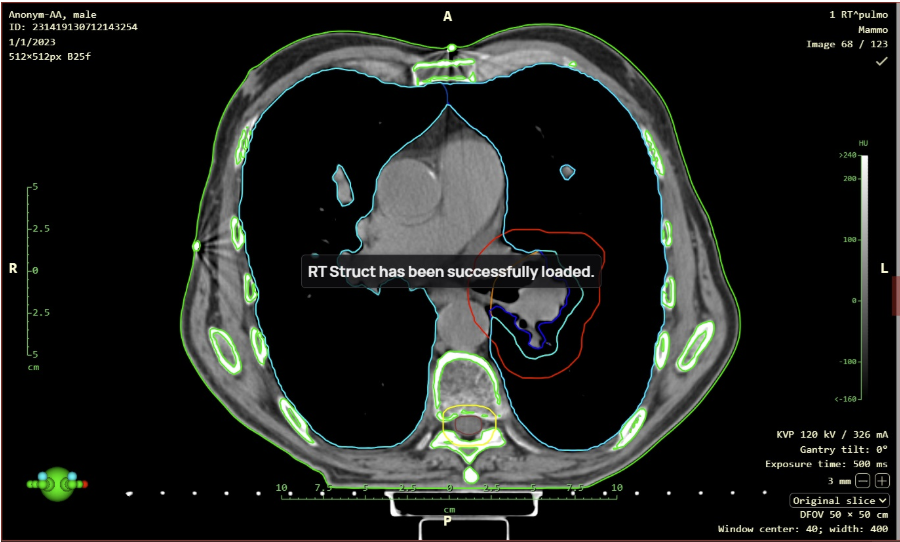

- Support for RTSTRUCT display with the “Load RT Struct” function, it is now possible to display Radiotherapy Structure (RTS) modality data, for example, a radiotherapy plan over a series of CT modality images. This function is called up by right-clicking on the RTS data displayed in the working set of images to bring up the context menu and then selecting the “Load RT Struct” action.